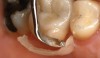

(3.) Maxillary premolar preparation.

Figure 3